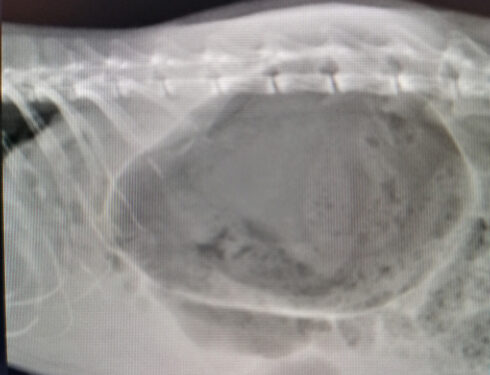

Emergency operation Gastric Volvulus Dilatation

In our surgery lesson: “You may see this case once in our professional life.” started by saying, Surgery Professor Kemal. After graduation; The first clinical…